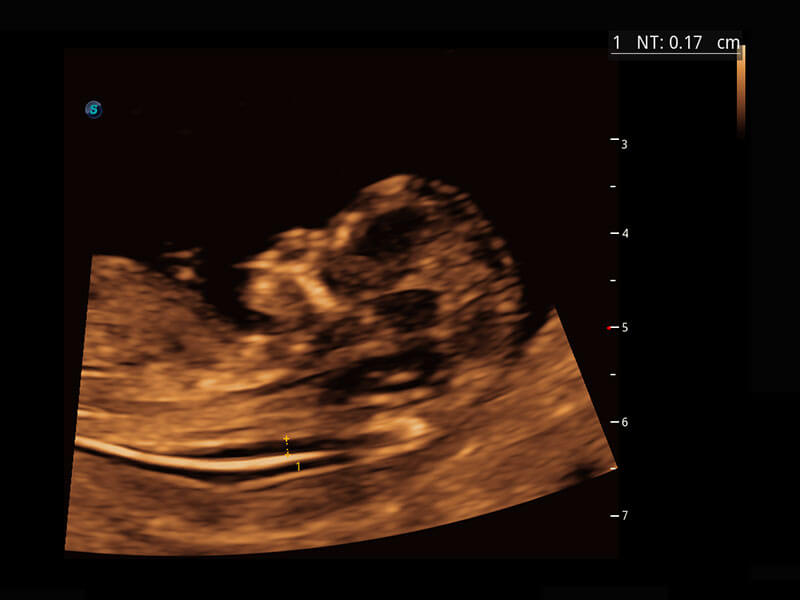

P60搭载一系列胎儿心脏成像技术,实现精细的胎儿心脏评估。

四腔切面

四腔心血流

右室双出口

胎心容积成像